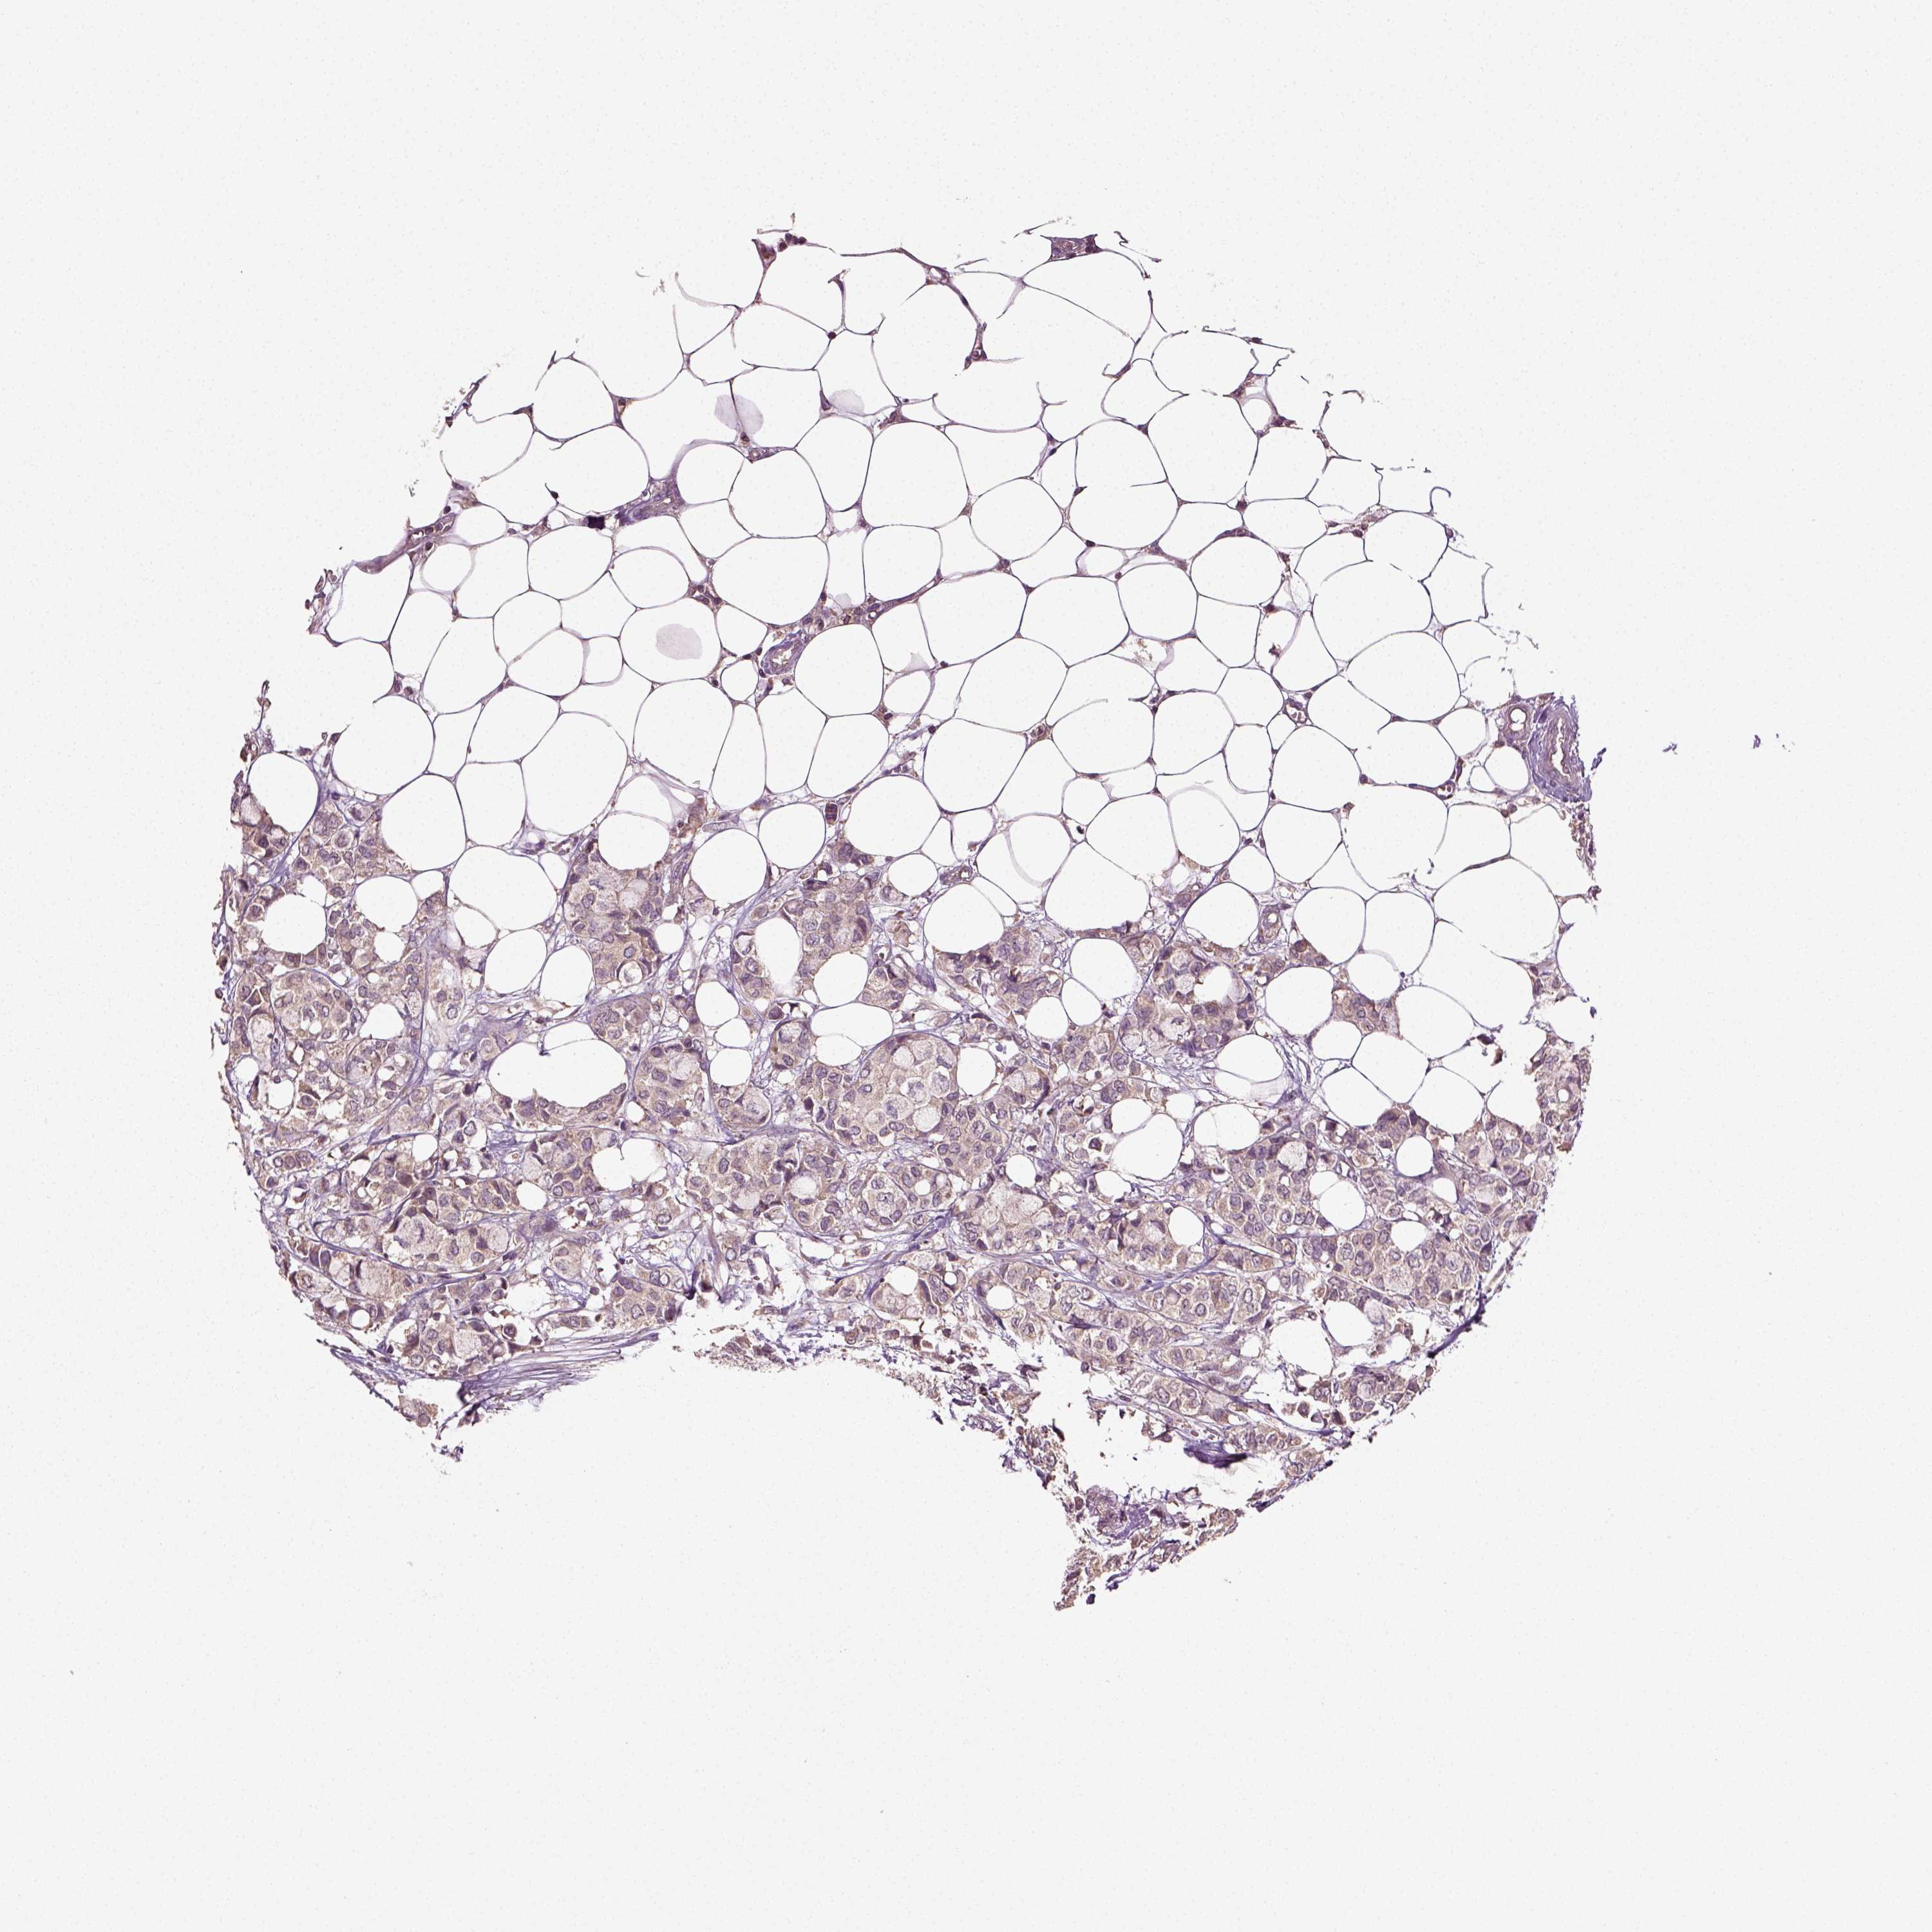

CANCER BREAST CANCER Show tissue menu

BRCA TCGA BRCA VALIDATION PROTEIN EXPRESSION